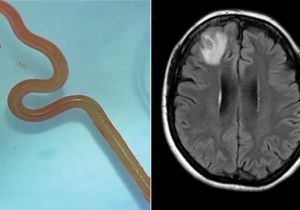

Oh My God! महिला के दिमाग में मिला 8 सेमी का जिंदा कीड़ा, डॉक्टर बोले- करियर का पहला हैरान करने वाला केस

29 Aug, 2023 03:40 PM IST | SAMIKSHASAGAR.COMऑस्ट्रेलिया ऑस्ट्रेलिया में एक महिला के दिमाग में जिंदा कीड़ा मिलने का हैरान कर देने वाला...